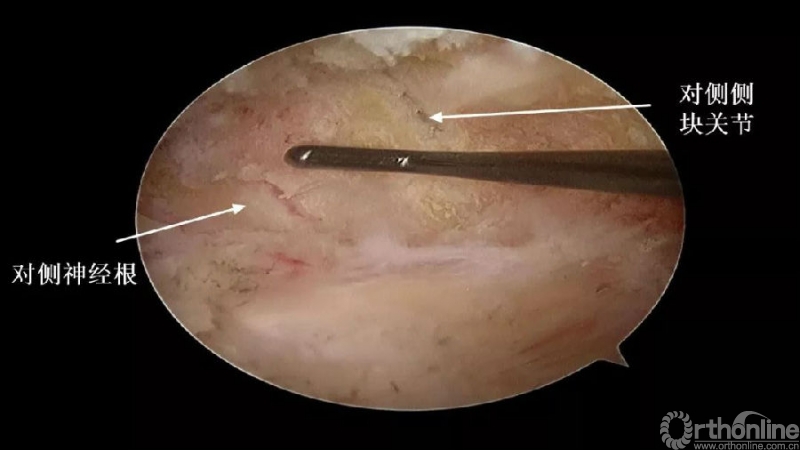

4.进一步加深移除骨赘的残余部分,直到显露出对侧的神经根及关节突关节的内壁;

3. 如何确定对侧结构?